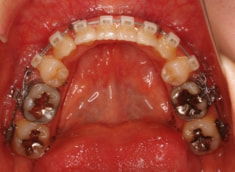

治療開始から約1年後

歯根のパラレリング(平行性)が獲得されております。

下顎8番は、両側抜歯済みです。